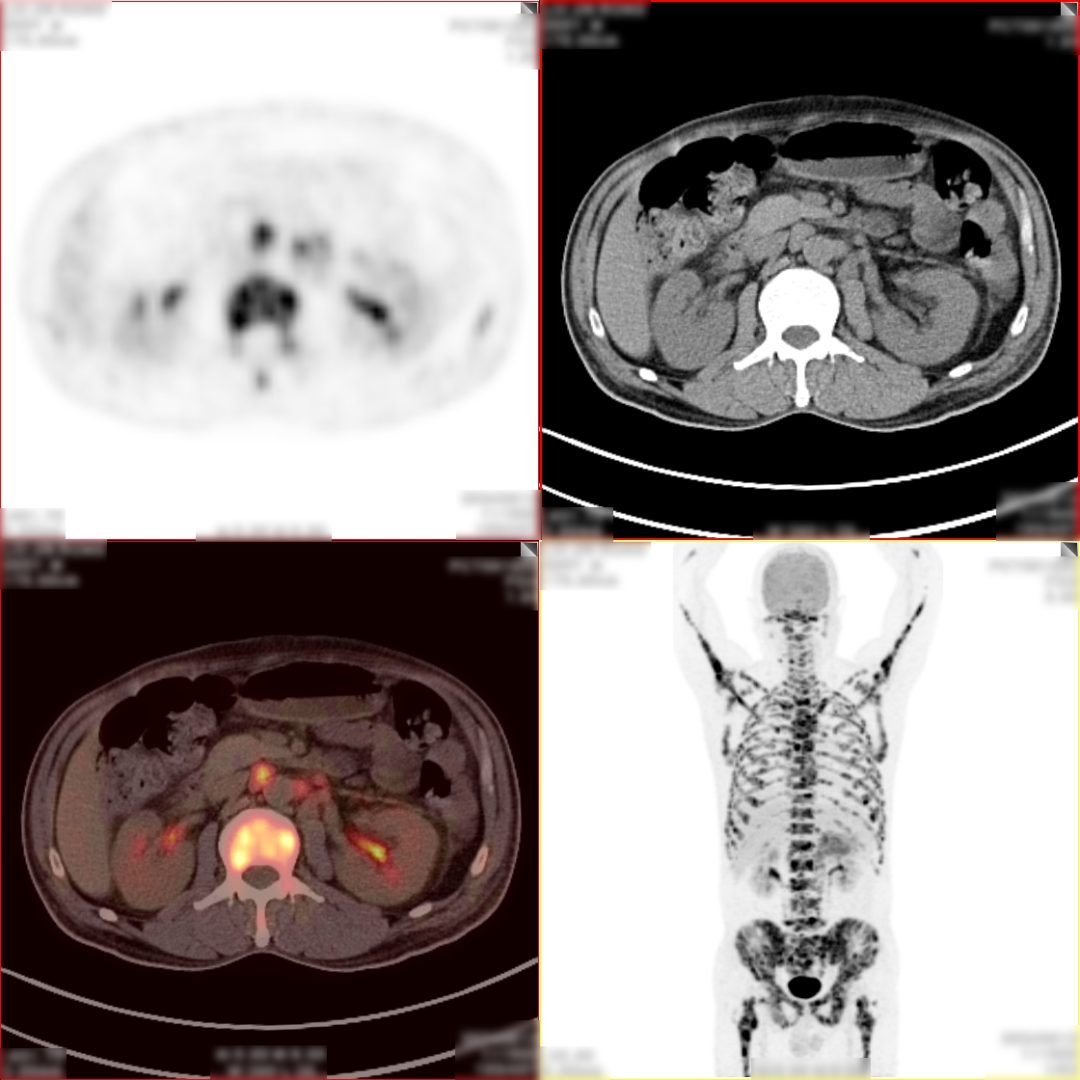

病史:男,55岁,腹痛伴乏力3天入院检查,MR:胰尾部肿物,考虑胰腺癌并多发淋巴结转移;超声胃镜下胰腺活检未见癌细胞,为了解全身状况申请PET检查。

PET/CT检查所见

空腹 6h 以上,静脉注射显像剂 18F-FDG,平静休息 60min 后行全身 PET 及 CT 断 层显像,解剖与功能图像行多层面、多幅显示,影像清晰。

PET/CT诊断意见:

1、胰腺体尾部块状胰腺癌,病灶侵犯相邻胃体部胃壁,并可能侵犯左侧肾周筋膜,肿块远端胰尾部胰管扩张;盆腔少量积液;

2、胰腺尾部周围、中上腹部腹膜后区腹主动脉周围及纵隔内(1R、1L、2R、4R、5、7 组)多发淋巴结转移灶;

3、双侧尺骨近端、双侧肱骨、右侧颞骨、枕骨、蝶骨、双侧下颌骨头、双侧锁骨、双侧肩胛骨、胸骨、脊柱各椎体、双侧各肋骨、骨盆诸组成骨、右侧股骨头、双侧股骨颈及股骨干广泛骨转移灶,其中左侧第 2、4 前肋、右侧第 4、7 侧肋病理性骨折。

PET/CT活检病理:胰腺癌